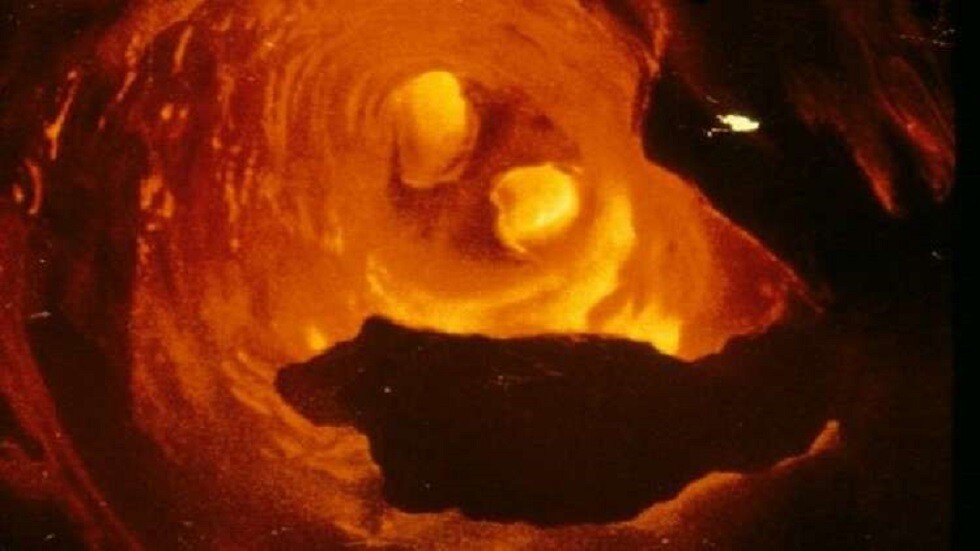

ووفقا للدكتورة، فإن تصلب الأوعية الدموية مرض مزمن تتشكل فيه لويحات تصلب الشرايين تدريجيا على السطح الداخلي للشرايين، ما يضيق تجويفها ويعيق تدفق الدم. ويمكن أن يكون الصداع وألم الصدر من أولى علامات المرض.

وتؤكد أنه للكشف المبكر عن تصلب الشرايين، يجب إجراء الفحوصات اللازمة في الوقت المناسب. وتنصح بإجراء فحص دم لمستوى الدهون، وفحص بالموجات فوق الصوتية للشرايين السباتية والدماغية والأطراف السفلية. ونظرا لأن الشرايين التاجية لا تظهر بالموجات فوق الصوتية، يُستخدم تصوير الأوعية التاجية لتقييم نفاذيتها وحالة القلب.